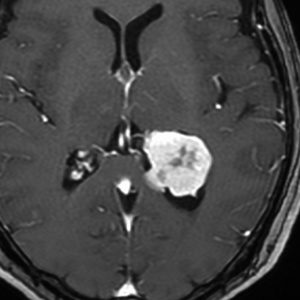

側脳室三角部髄膜腫 lateral ventricle (trigon) meningioma

50歳くらいの女性に偶然発見された三角部髄膜腫です。この部位はとても巨大にならないと症状が出ないので,しばらく様子を見ることにしました。

5年後です。増大傾向が止まりません。大きくなると手術リスクがすごく高くなるので,開頭手術で摘出することにしました。

右側は,手術翌日のMRIです。頭頂部の皮質経由で腫瘍は全摘出できています。専門的には,頭頂部経皮質到達法 parietal transcortical approach, high-parietal approachといいます。この患者さんは幸い頭頂葉症状は全く出ませんでした。でも巨大な三角部髄膜腫になると頭頂葉症候が手術後遺症として残ることがあります。でも慎重な手術をすれば日常生活に大きな支障となることはほとんどないでしょう。